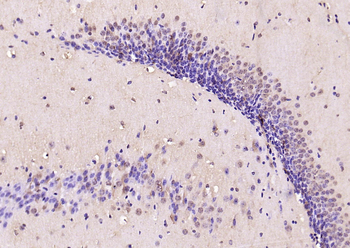

100 μl, 200 μl, 50 μlPhospho-SMAD5 (Ser463 + Ser465) Recombinant Rabbit Monoclonal Antibody [orb559123]

ICC, IF, IHC-Fr, IHC-P, WB

Mouse, Rat

Human, Mouse, Rat

Rabbit

Recombinant

Unconjugated

50 μl, 100 μlPhospho-Smad3 (Thr179) Rabbit Polyclonal Antibody [orb313112]